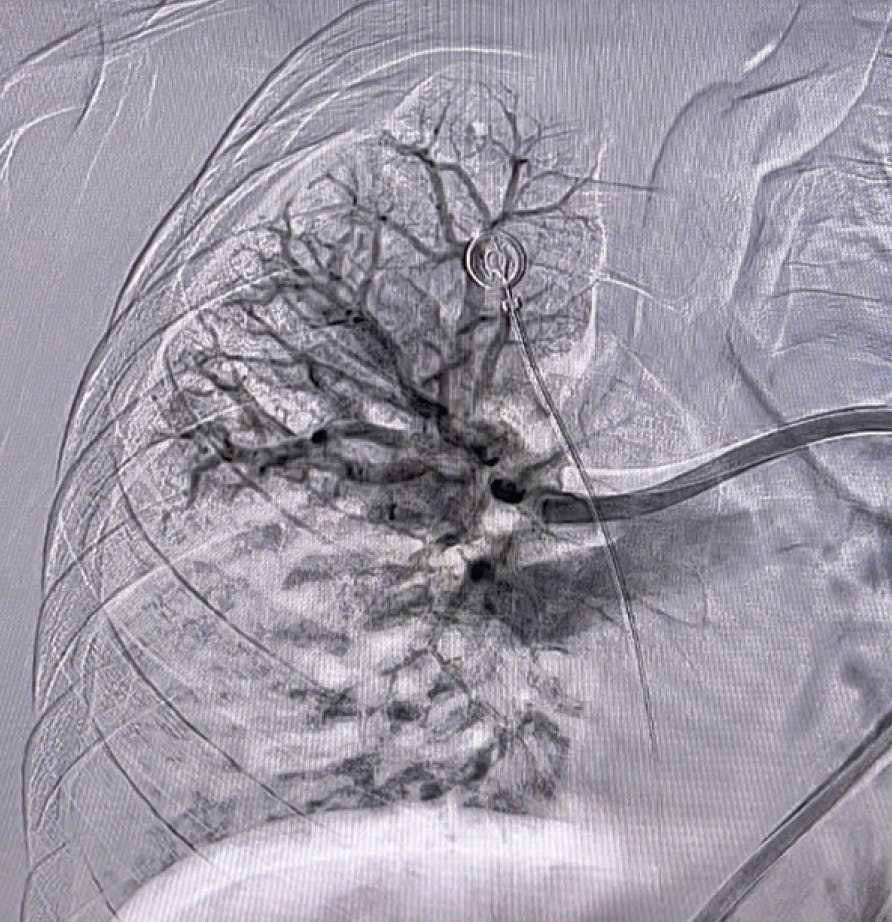

Based on evaluation, we decided to pursue aspiration thrombectomy utilizing Lightning Flash through a 16-F, 65-cm Gore DrySeal sheath (Gore & Associates). We achieved access in the right femoral vein. The device time was 17 minutes, and the total procedure time was 30 minutes (Figure 3, Figure 4, Figure 5, and Figure 6). At the conclusion of the case, the total EBL was 175 mL, the patient had BP of 112/67 mm Hg, HR of 65 bpm, and oxygen saturation of 99% on 3 L nasal cannula.

Figure 3. Post-thrombectomy lower right lobe angiogram.

Figure 4. Post-thrombectomy upper right lobe angiogram.

Figure 5. Post-thrombectomy left lobe angiogram.

INTERVENTION

Based on the evaluation, the decision was made to pursue aspiration thrombectomy using the Lightning Flash device. The opening PA pressures were 33/12 mm Hg (mean, 20 mm Hg) and closed with 18/3 mm Hg (mean, 8 mm Hg), taken through the 16-F, 65-cm Gore DrySeal sheath, showing a significant drop in pressure. The device time of Lightning Flash was 6 minutes, and the total procedure time was 55 minutes (Figure 3, Figure 4, and Figure 5). By the conclusion of the case, the EBL was 100 mL and postprocedure BP was 122/63 mm Hg, HR was 54 bpm, and oxygen saturation was 97% on 2 L nasal cannula.

Figure 3. Right post-thrombectomy angiogram.

Figure 4. Left post-thrombectomy angiogram.

After initial evaluation, the decision was made to use aspiration thrombectomy to remove the PE thrombus. We utilized a 16-F, 65-cm Gore DrySeal sheath through the right femoral vein. Penumbra’s Lightning Flash was used for a device time of 10 minutes (Figure 3, Figure 4, and Figure 5). The total procedure time was only 20 minutes. With the conclusion of the case, we had an EBL of 120 mL and a postprocedure BP of 120/87 mm Hg. The HR decreased substantially to 98 bpm, and the oxygen saturation improved to 100% on room air.